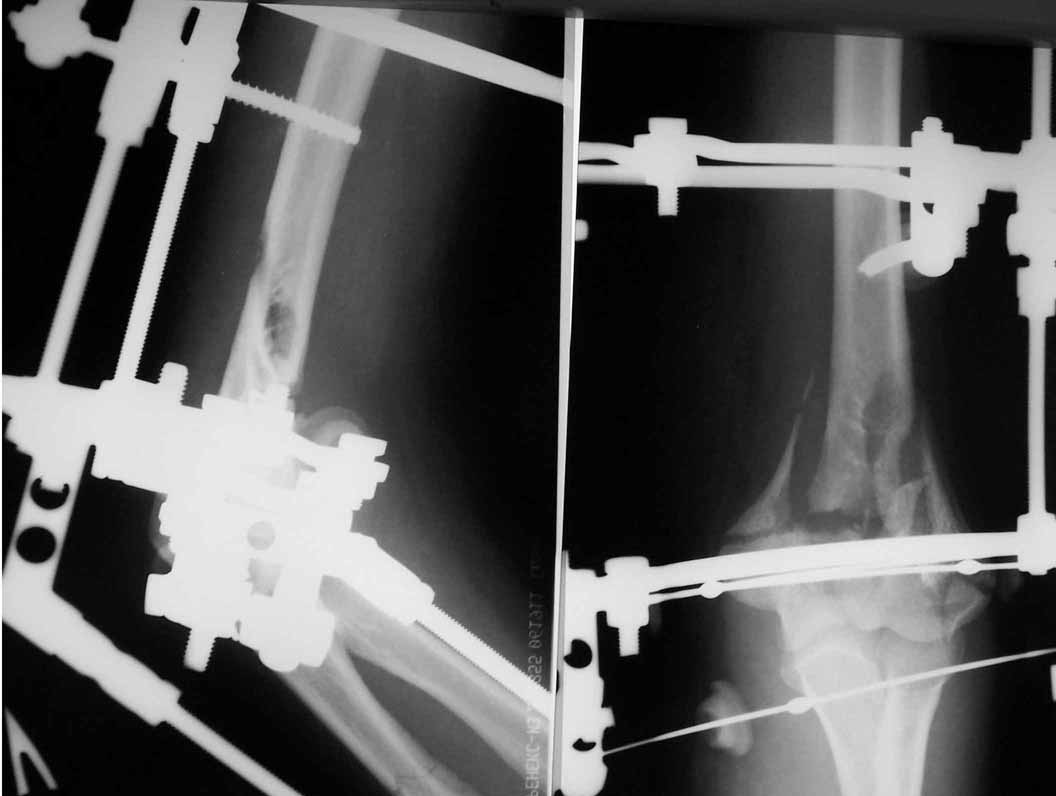

Женщина 42 лет, операция через неделю после перелома.

Д-з - открытый перелом мыщелков со смещзением и локтевой кости

без смещения - падение с лошади.

Остеосинтез закрытый (если так можно выразиться), т.е. без

разрезов. Длительность операции - около 1,5 часа со студентом.

6 щелчков ЭОПом.

И как часто вам удается получить такую симпатичную рентгенологическую картинку при Т-образных переломах, особенно с импрессией суставной поверхности? А без ЭОПа? Какого обьема движений достигаете в итоге?

МА> И как часто вам удается получить такую симпатичную рентгенологическую

МА> картинку при Т-образных переломах ,

Мой опыт не могу назвать исчерпывающим - где-то 7-8 наблюдений.

Всегда получалось хорошо. У меня сохранились несколько прослеженных "от и до" случаев - отцифрую и вышлю.